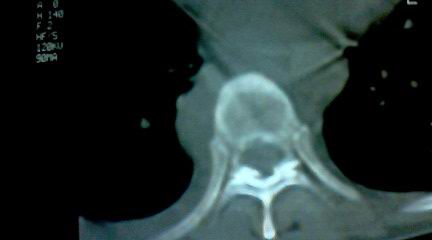

标题: CT25218:请教!胸部CT,胸8椎体骨质破坏,伴周围软组织肿。

患者,女41岁,肢体乏力。

两肺上叶继发性肺结核;胸椎结核并椎旁寒性脓肿形成。

胸椎结核并椎旁寒性脓肿形成。

恶性,椎体淋巴瘤或pnet并肺内转移。